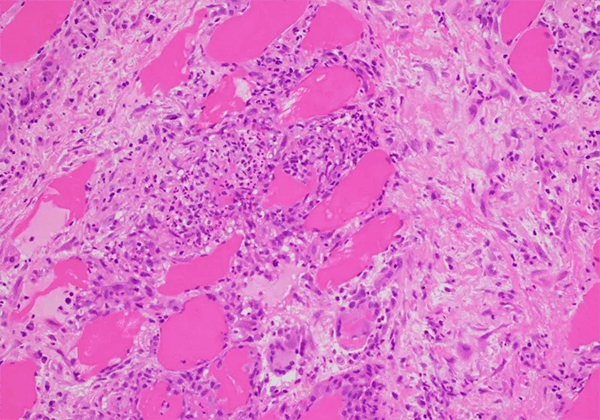

½á½Ú²¡ÊÇÒ»ÖÖ²¡Òò²»Ã÷µÄÂýÐÔ¶àϵͳÑ×ÐÔ¼²²¡£¬£¬£¬£¬ÌØÕ÷Ϊ·Ç¸ÉÀÒÑùÉÏÆ¤ÑùÈâÑ¿Ö×£¬£¬£¬£¬°éÓе¥¸öºËϸ°û½þÈóºÍ΢½á¹¹ÆÆË𡣡£¡£¡£¸Ã²¡¿ÉÀÛ¼°Æ¤·ô£¬£¬£¬£¬ÑÛ¾¦£¬£¬£¬£¬ÐÄÔàºÍÖÐÊàÉñ¾ÏµÍ³£¬£¬£¬£¬Áè¼Ý90%µÄ²¡ÀýÀÛ¼°·Î²¿¡£¡£¡£¡£¸Ã¼²²¡ÊÇÖØ´óµÄ¡¢Î´Öª×ãµÄÒ½ÁÆÐèÇóÖ®Ò»¡£¡£¡£¡£